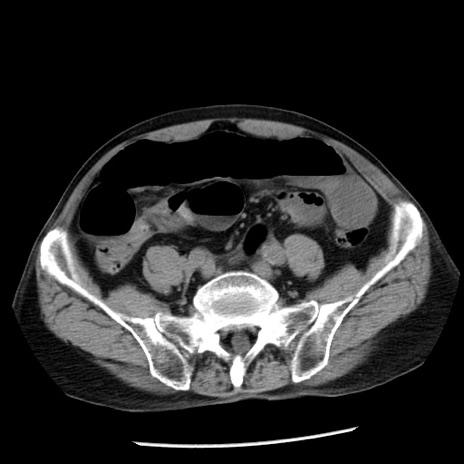

症例26(横断像)

【症例】80歳代男性

【主訴】嘔吐

【現病歴】昨晩2回嘔吐あり、今朝になっても嘔吐あり。来院。

【既往歴】胃潰瘍

【身体所見】意識清明、BT 37.6℃、BP 166/95mmHg、HR 100bpm、SpO2 97%、腹部:平坦・軟、腸蠕動音聴取良好、圧痛なし。

【データ】WBC 21900、CRP 1.46